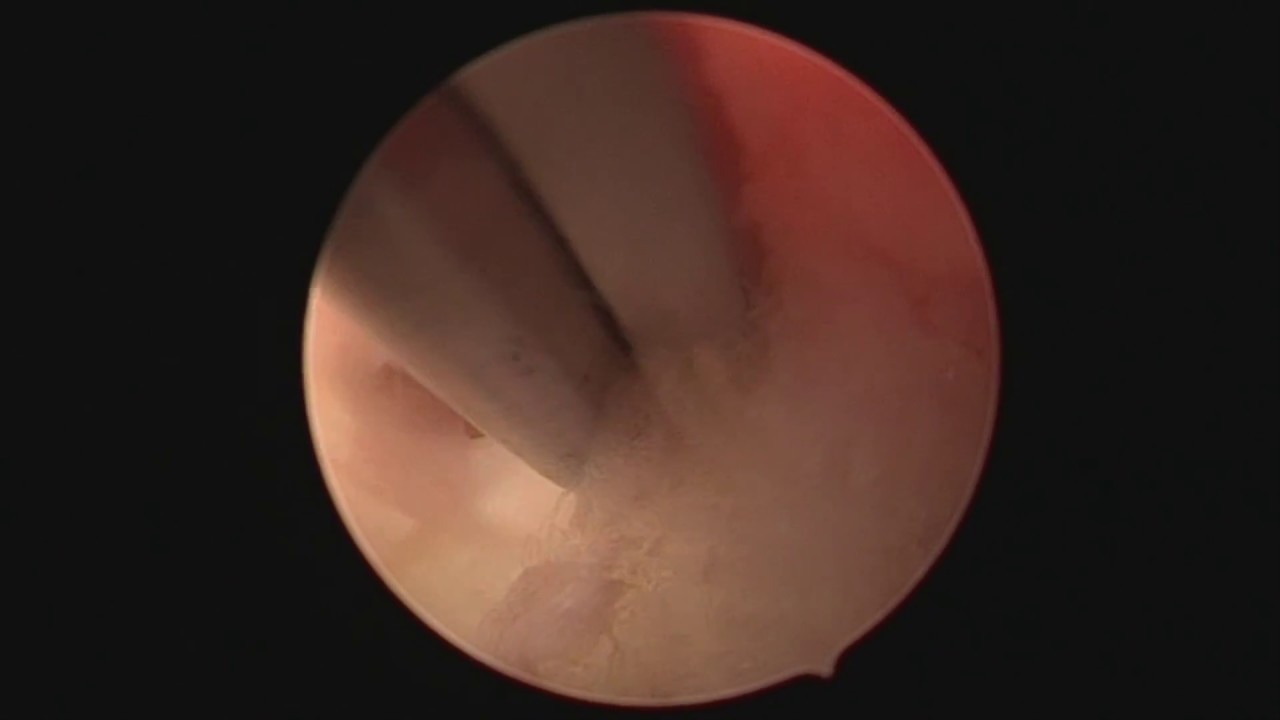

• Tratamento por Endoscopia Hérnia de disco O paciente vai ao hospital 1h antes do procedimento Duração 30-40min Feito sob sedação, anestesia local e sem necessidade de anestesia geral Introduzimos uma fina câmera pela qual passam pequenas pinças. Com imagens de altíssima qualidade podemos remover a hérnia de disco e deixar os nervos livre da compressão Devido à via de acesso especial, o paciente tem sua dor tratada Sem agressão aos músculos, Sem retirada de ossos ou articulações da coluna e Sem a colocação de pinos ou próteses Incisão de 7mm e apenas 01 pontos para o fechamento da pele 2 horas após o procedimento, liberado para casa Andando normalmente Retorno ao trabalho após 48h

A Clínica Coluna e Neuro é especializada em tratar traumas e patologias relacionadas à coluna vertebral, além de neurocirurgia. Dentre os procedimentos realizados, destacam-se as cirurgias minimamente invasivas, como a cirurgia endoscópica da coluna, eficaz no tratamento de hérnias discais. Essa técnica permite a descompressão dos nervos espinhais e a remoção do material discal de forma segura, minimizando o trauma cirúrgico.